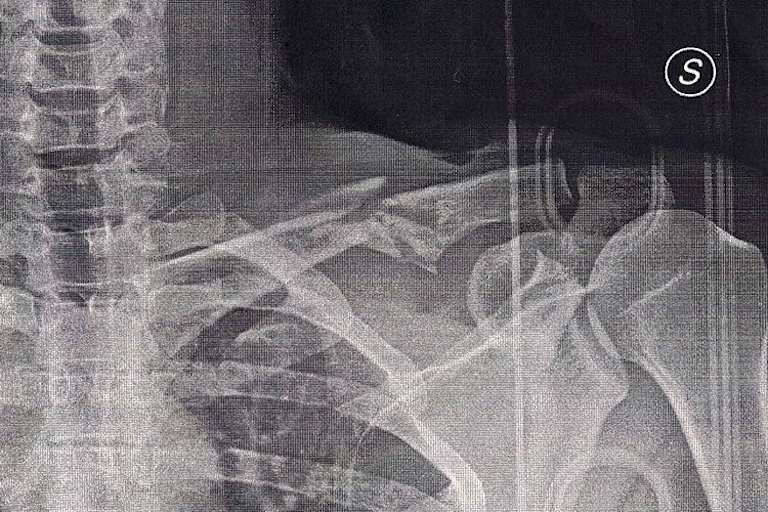

Das erste Superbike-Rennen forderte in den Reihen der österreichischen Teilnehmer ein weiteres Opfer. Nach dem sechsten Rang im Training riskierte Wolfgang Gammer in der Startrunde zu viel und rutschte von der Strecke. Im Krankenhaus von Adria wurde ein Bruch des Schlüsselbeins festgestellt. "Die Schmerzen sind momentan ziemlich heftig", erzählt der oberösterreichische BMW-Pilot gegenüber SPEEDWEEK.com. "Obwohl sich der Bruch seit Samstag weiter verschoben hat, hat mir ein Arzt geraten, mich nicht operieren zu lassen. Ich hole mir jetzt noch eine zweite Meinung und danach werde ich eine Entscheidung treffen."

Noch hofft Gammer, am 30./31. Mai beim Auftakt zur österreichischen Meisterschaft auf dem Pannonia-Ring fahren zu können. "Die Konkurrenz ist auch dieses Jahr wieder extrem stark. Auch mit meiner Verletzung traue ich mir zu, einige Punkte holen zu können. Diese könnten am Ende der Saison entscheidend sein."